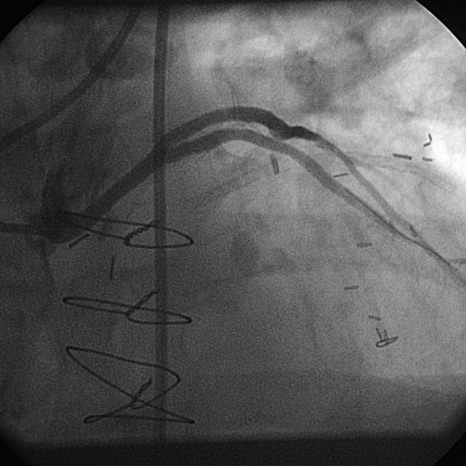

PCI of the vein and arterial grafts have unique challenges. For any PCI, guide support is very important for successful balloon and stent delivery. In a tortuous vein graft with a steep angle, advancement of a stent can be very difficult and challenging. Therefore, it is important to choose the best available catheter before starting PCI. Similar to the right coronary angiography, a JR4 guide catheter is most commonly used in this setting. However, Amplatz guide catheters for left vein grafts and multipurpose catheters for right vein grafts are better choices in certain anatomy. In Figure 8 and Figure 10 two examples of poor guide support in two vein graft interventions can be seen. Initially, a JR4 guide was used for PCI of the vein graft supplying the left anterior descending artery (LAD) without any success. However, after changing the guide to an Amplatz left 2 guide catheter, we achieved excellent support without any difficulty in advancing two stents (Figure 9). In Figure 10, difficulty is illustrated in engaging the vein graft ostium supplying the right coronary artery with a JR4 catheter. This vein graft has a very steep inferior take off from the aorta. After changing the guide to a multipurpose catheter, we were able to deliver three stents successfully without any difficulties (Figure 11). Similar challenges exist in the treatment of the left IMA or right IMA. These arterial grafts can be extremely tortuous making stent delivery very difficult. It may be necessary to use short length stents for a better deliverability or stents with lowest profile. Usually, similar to the native coronary intervention, a 6 French guide is appropriate for the routine use.

Balloon angioplasty and stenting:

In order to minimize distal embolization, primary stenting without previous angioplasty is recommended in vein graft interventions. However, in angulated and very high grade lesions, stent without balloon angioplasty may not be able to cross a lesion requiring balloon angioplasty before stenting. Balloons should be sized smaller in order to prevent rupture or dissection. Once an angioplasty balloon is advanced across the lesion, usually it is inflated to 6 or 8 atmospheres for few seconds. Stenting is similar to the balloon. Once a stent is placed across the lesion, it is inflated to higher pressures such as 12-14 atmospheres. The use of a bare metal or drug eluting stents in vein grafts is controversy. This topic is discussed in detail in the restenosis chapter. Angioplasty and stenting of bifurcation sequential vein grafts at the site of the bifurcation or distal to the graft is challenging and usually requires more complex interventions including double wiring and utilization of two stents. A comprehensive classification with guide to interventional techniques for bifurcation lesions is published recently that can be used as a guide for bifurcation lesions interventions involving vein grafts [1].